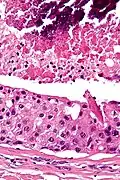

Their histologic appearance is similar to ductal breast carcinoma.